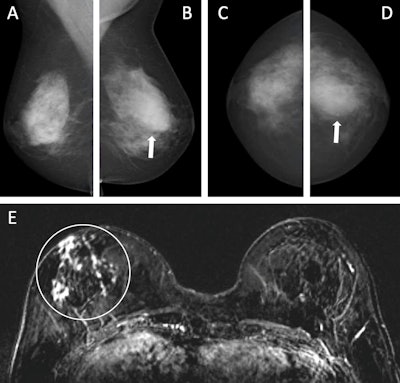

Images depict a 55-year-old woman with a family history of breast cancer who underwent combined mammography and MRI screening. (A) Right and (B) left mediolateral oblique and (C) right and (D) left craniocaudal mammograms show a large known cyst in the left breast (arrow in B and D), but were otherwise assessed as being unremarkable. Breast tissue was judged to be extremely dense. (E) Concurrent axial subtraction MRI scan shows a large, diffuse, invasive lobular cancer (circle) in the right breast. The AI system provided a case-based cancer suspicion score of 8 on a scale of 0-10, which would have led to selection for MRI screening using both the score 5 and score 8 thresholds, but not the score 9 threshold.RSNA